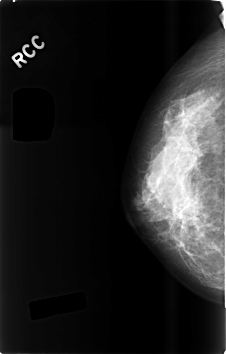

C_0494_1.RIGHT_MLO

RIGHT_CC LINES 4600 PIXELS_PER_LINE 2928 BITS_PER_PIXEL 12 RESOLUTION 50 NON_OVERLAY

RIGHT_MLO LINES 4568 PIXELS_PER_LINE 2920 BITS_PER_PIXEL 12 RESOLUTION 50 NON_OVERLAY